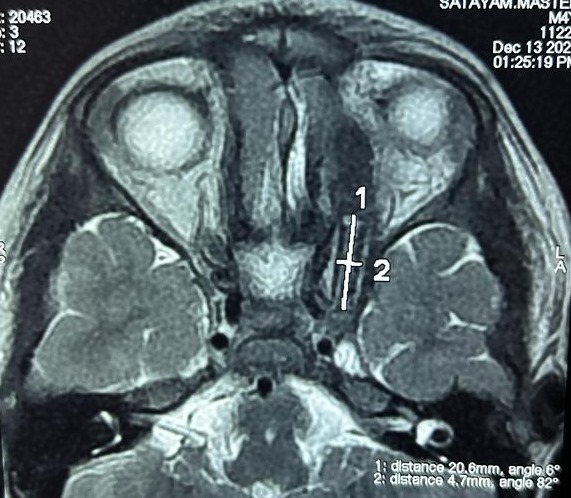

Finally, a desperate journey led the boy and his farmer father to Chennai. They were referred to SIMS Hospital, On examination of the MRI, specialists uncovered the reason behind the persistent infection: a 3-cm wooden stick lodged deep within the eye, extending into the cavernous sinus and dangerously close to the brain’s crucial blood vessels. Previous diagnoses missed this vital detail, jeopardising the child’s health with every passing day.

The stick’s location presented a monumental challenge. Traditional open-brain surgery carries significant risks. The Neuro team at SIMS Hospital boldly opted for a breakthrough solution: Endoscopic Endonasal surgery. This minimally invasive technique, typically used for brain tumour removal, was deployed to access the orbit and remove the stick through the right nostril, significantly reducing complications and recovery time.

Leveraging cutting-edge Neuro navigation and precision-guided technique, Dr. Vishwaraj Ratha, Senior Consultant, Neuro surgeon and Dr. Senthil Kumar, Senior Consultant Neuro Anaesthetist, at SIMS Hospital achieved a minimally invasive feat. Through a nasal endoscopic approach, they navigated the intricate sections of the orbit and successfully retrieved the foreign body, minimising collateral disruption and enabling rapid patient recovery within 48 hours. This pioneering intervention stands as a testament to the transformative power of advanced surgical technology in achieving optimal outcomes with minimal scar.